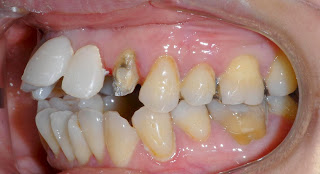

↑上の犬歯は、まだ抜いてません。

差し歯の下の、金属の芯が、むき出しで見えている。

↑上の犬歯は、まだ抜歯していない。

差し歯の下の、金属芯がむき出しになっています。